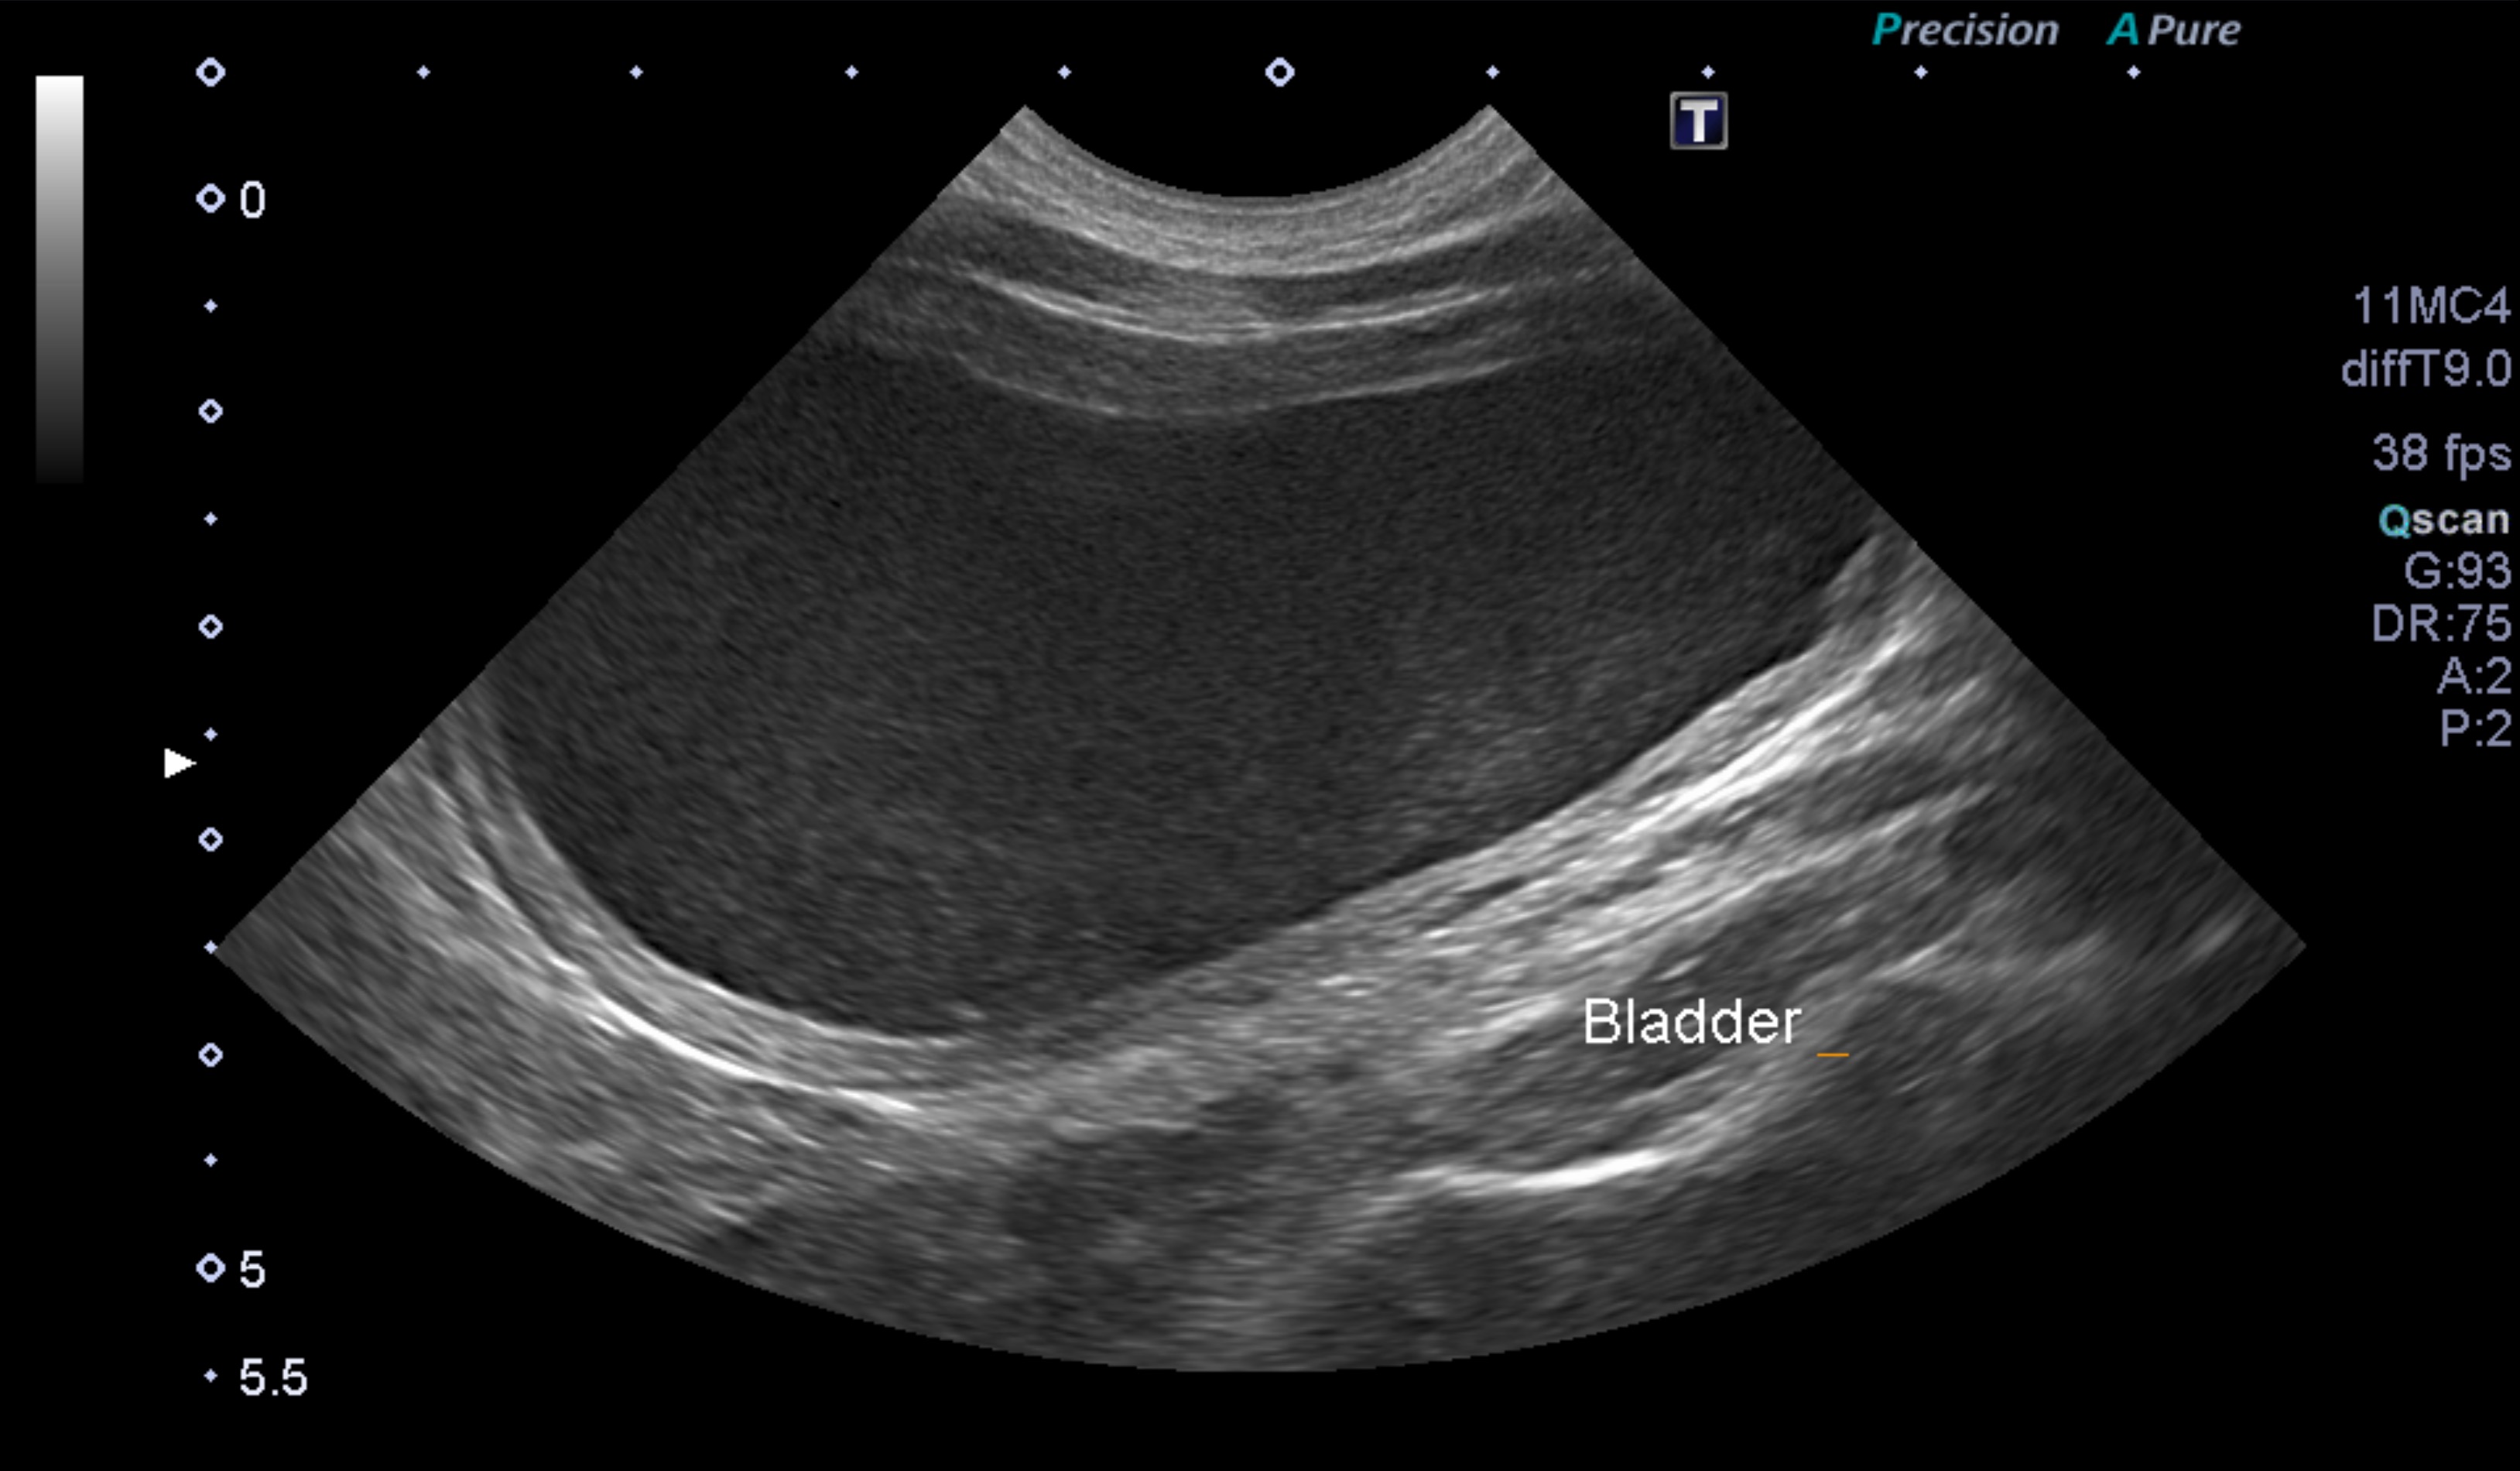

超音波検査でも、膀胱内の尿が綺麗になっているのが確認できます。